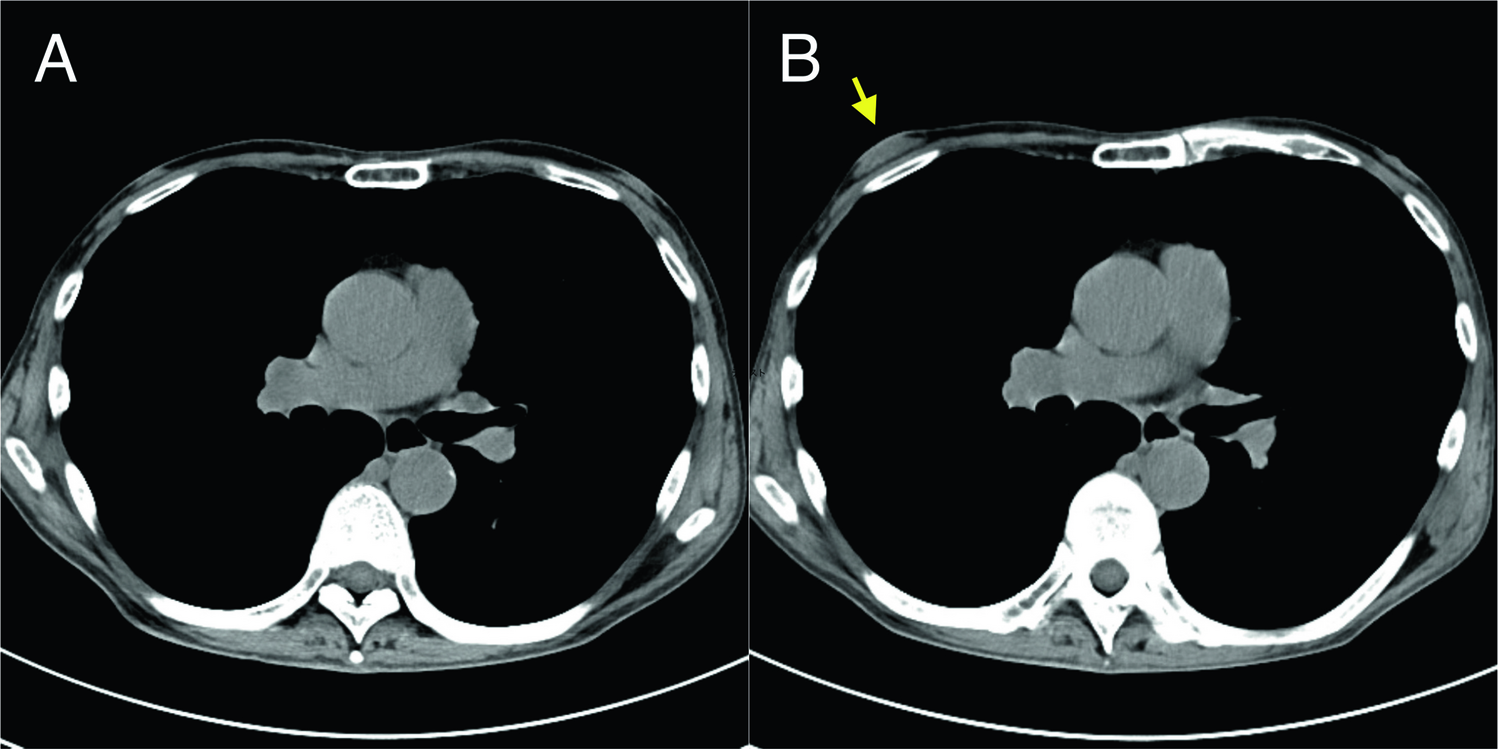

A 65-year-old man with rheumatoid arthritis in sustained remission presented with a two-week history of right breast swelling. He had been receiving oral methotrexate (MTX) at a stable dose of 14 mg/week, oral folic acid 5 mg/week for over a year, with good adherence. Concomitant therapies, including prednisolone, sulfasalazine, tacrolimus, and adalimumab had been adjusted during the disease course (Supplementary Fig. 1). Medical history was otherwise unremarkable. Physical examination revealed a rubbery, concentric mound of tissue beneath the right nipple-areolar complex, although not apparent on visual inspection. Non-contrast-enhanced chest computed tomography demonstrated newly developed glandular tissue in the right subareolar area, compared with imaging obtained before treatment (Fig. 1A and 1B). Ultrasonography revealed diffusely distributed glandular tissue within the adipose tissue (Supplementary Fig. 2A). These findings were consistent with gynecomastia. Hepatic, renal, and thyroid functions were unremarkable. Serum levels of sex hormones, such as testosterone, estradiol, sex hormone-binding globulin, luteinizing hormone, and follicle-stimulating hormone were within normal limits. Normal levels of human chorionic gonadotropin, dehydroepiandrosterone, and prolactin ruled out testicular, adrenal, and pituitary tumors. Core needle biopsy excluded malignancy. Given the stable disease activity for 6 months, the MTX dose was reduced to 6 mg/week, while other medications were unchanged. The breast swelling improved over four months, which was confirmed by clinical examination and ultrasonography (Supplementary Fig. 2B). The clinical course suggested a probable association between methotrexate and gynecomastia.

Fig. 1

Non-contrast-enhanced chest computed tomography. A Before initiation of methotrexate therapy, showing no abnormal glandular tissue in the bilateral subareolar areas. B After 17 months of low-dose methotrexate therapy, demonstrating newly developed unilateral glandular enlargement in the right subareolar area (arrow), consistent with gynecomastia